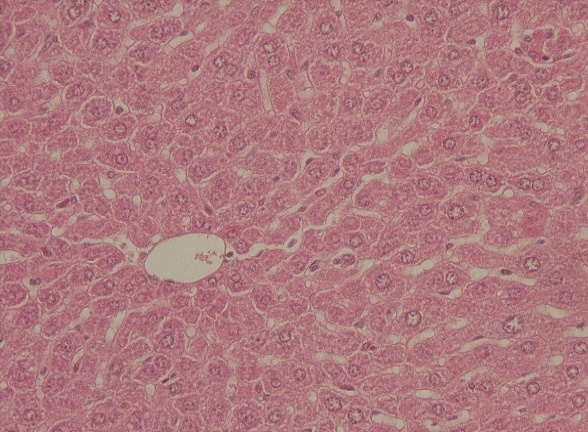

Histopathological studies

Histological examination revealed that there were no changes observed due to the 90-day CSE administration in liver, heart, and the kidneys.

Fig. 1: Cross section of A. normal B. CSE 1100 mg/kg/d treated mouse liver and kidney (staining with HandE)

The histology of all organs did not show any change after the administration of CSE at 275-1100 mg/kg/day. This makes CSE perspective as a standardized herbal medicine for male contraception. Histological changes in vital organs should receive serious attention. Herbal medicines, which are administered as contraception, are expected not to affect vital organs, such as liver, heart, kidney, stomach and intestines. Gossypol, which used to be a candidate of contraceptive medicine, causes various histological disorders in several organs. When gossypol was administered at 1 mg/kg/day for 130 d to dogs, death occurred, accompanied by myocarditis and endocarditis. If the dosage is increased to 3 mg/kg/day, cardiac hypertrophy, congestion of kidney and spleen, fatty degeneration and liver necrosis will occur, exacerbated by edema and hemorrhage of the lungs [15]. The administration of Abrus precarious extract at 400-1600 mg/kg/day for 18 d also leads to liver disorder, which is lymphocytic infiltration in vena portae [16]. Both gossypol and Abrus precatorius are candidates of male contraception. It is suspected that in Abrus precatorius, there is not only glycyrrhizin, which prevents spermatogenesis, but also ricin and abrin, which may be toxic to the liver [17].

Similar to the result of acute toxicity of CSE [4], no histological change was discovered in the tests of test animals which were administered with CSE at 275-1100 mg/kg/day for 90 d. It showed the safety of CSE as a prospective herbal contraceptive medicine given in the medium term.